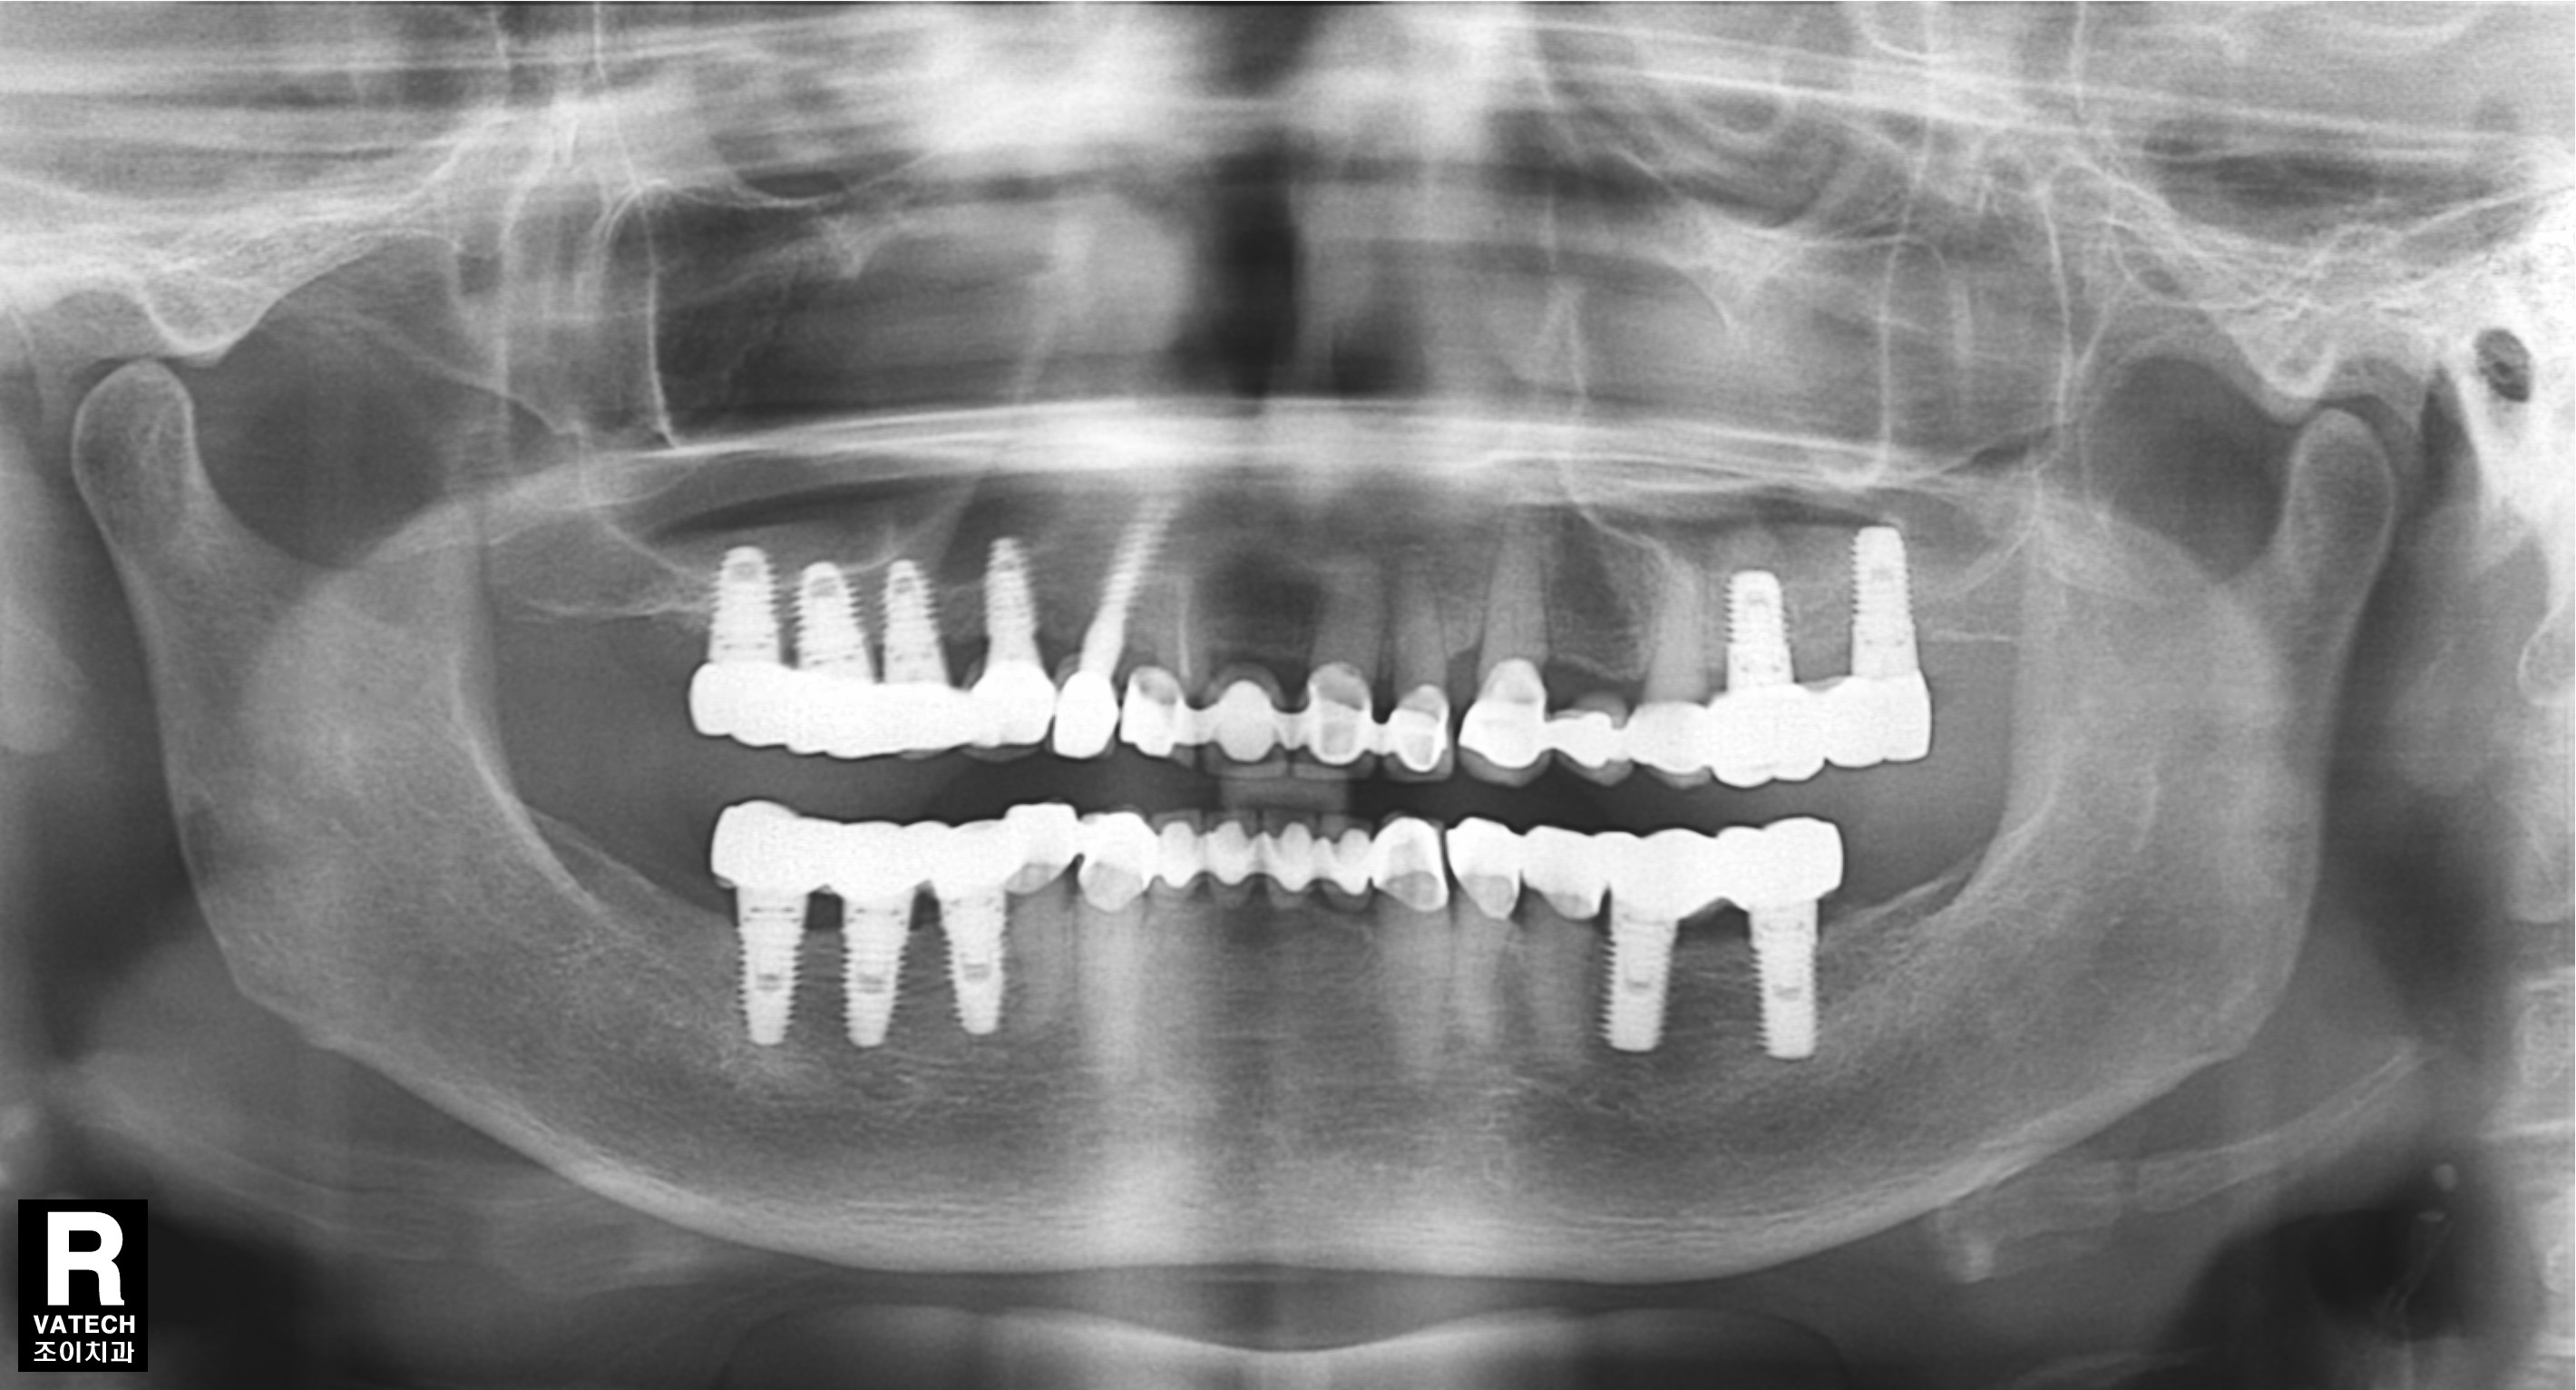

[임플란트] 제목 : 부분틀니 벗기

라식해서 안경을 벗듯이, 임플란트해서 틀니를 벗은 경우입니다.

요즘은 임플란트가 있으니 야예 틀니를 하지 않는 것이 더 좋은 방법일 듯 합니다.